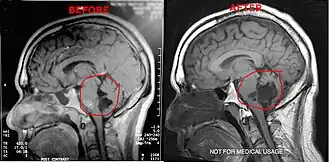

Diagnosis

Magnetic resonance imaging (MRI) and computed tomography (CT) brain scans can be used to identify these tumors.